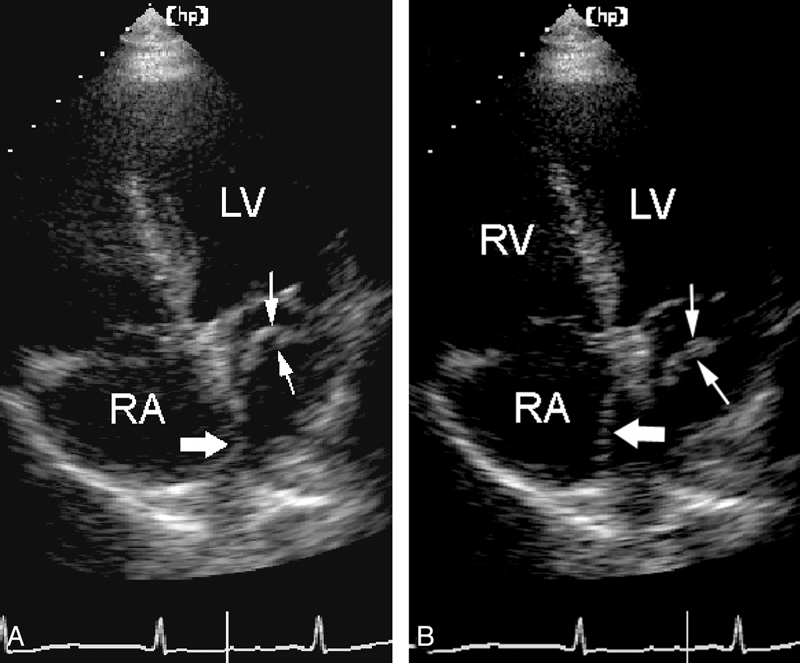

فحوصات تشخيصية لبعض امراض القلب والشرايين التاجية